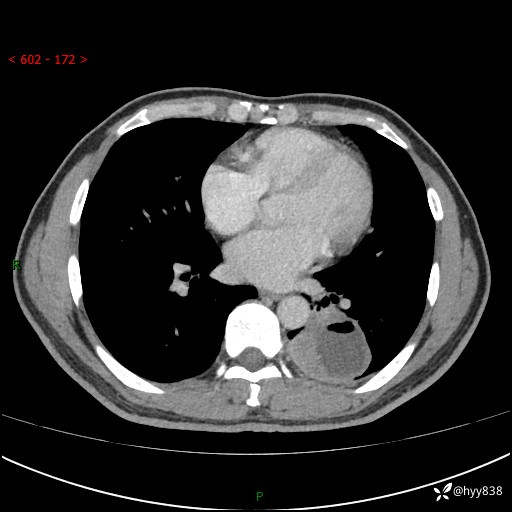

胸部CT平扫

增强